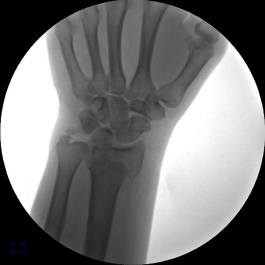

患者男,48岁,主诉外伤致右腕部疼痛,活动受限7天。于南阳市骨科医院行手法整复后患者对治疗效果不满意,遂手术治疗。